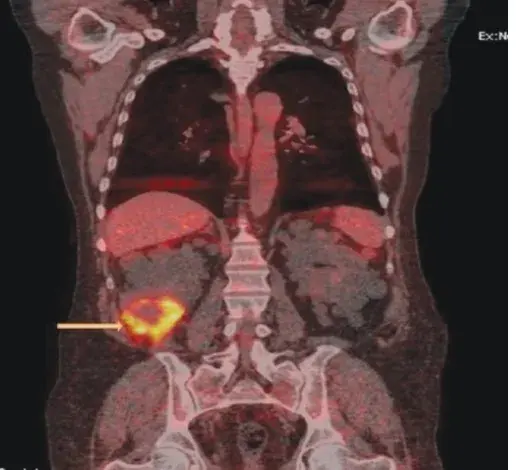

Jovem com hipertensão e massa abdominal